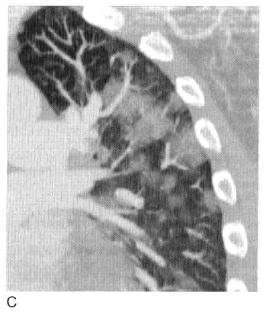

图6 实变:CT血管造影征

肺炎患者增强CT显示局灶性实变,与实变肺组织相比,不透明的动脉(箭头所示)密度增大,实变边界在斜裂后部分出现